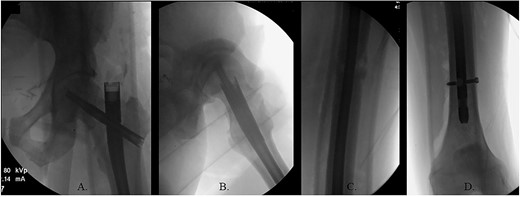

(A) AP radiograph of left hip with implant; (B) lateral radiograph of left hip with implant; (C) reduced fracture site with implant; (D) distal femur with implant.

The hip was extended, and a ball-tipped guidewire was successfully passed across the fracture site to a center–center positionwithin the canal at the level of the knee (Fig. 4C and D). Sequential 0.5-mm reaming from 9 to 13 mm prepared for an 11 × 400 mm, 125° Gamma3® intertrochanteric rod (Stryker© Kalamazoo, MI), with a 95-mm cephalomedullary screw and ×2 distal lateral to medial interlocking 5.0-mm screws (Fig. 5A–D). Through the course of the procedure, 400 cc of blood loss necessitated two units of packed red blood cells.

The patient immediately was weight-bearing as tolerated to the operative extremity and worked with physical therapy (PT) to include 80 ft on post-operative day (POD) #2 with use of a front-wheeled walker. He continued to progress with PT and was discharged home POD #8 with home health/PT. At 12 months, the patient denied pain, and XRs demonstrated robust callus formation and bridging healing at the fracture site (Fig. 6).

(A) 12-month post-operative AP radiograph of left hip; (B) 12-month post-operative lateral radiograph of left hip; (C) 12-month post-operative lateral femur radiograph; (D) 12-month post-operative AP distal femur radiograph.